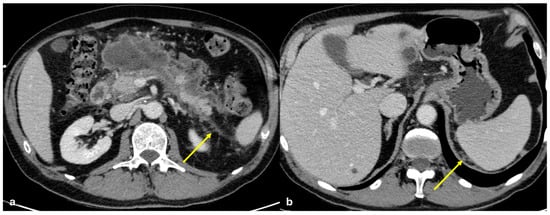

3.3.4. Subperitoneal Spread of Necrotizing Pancreatitis